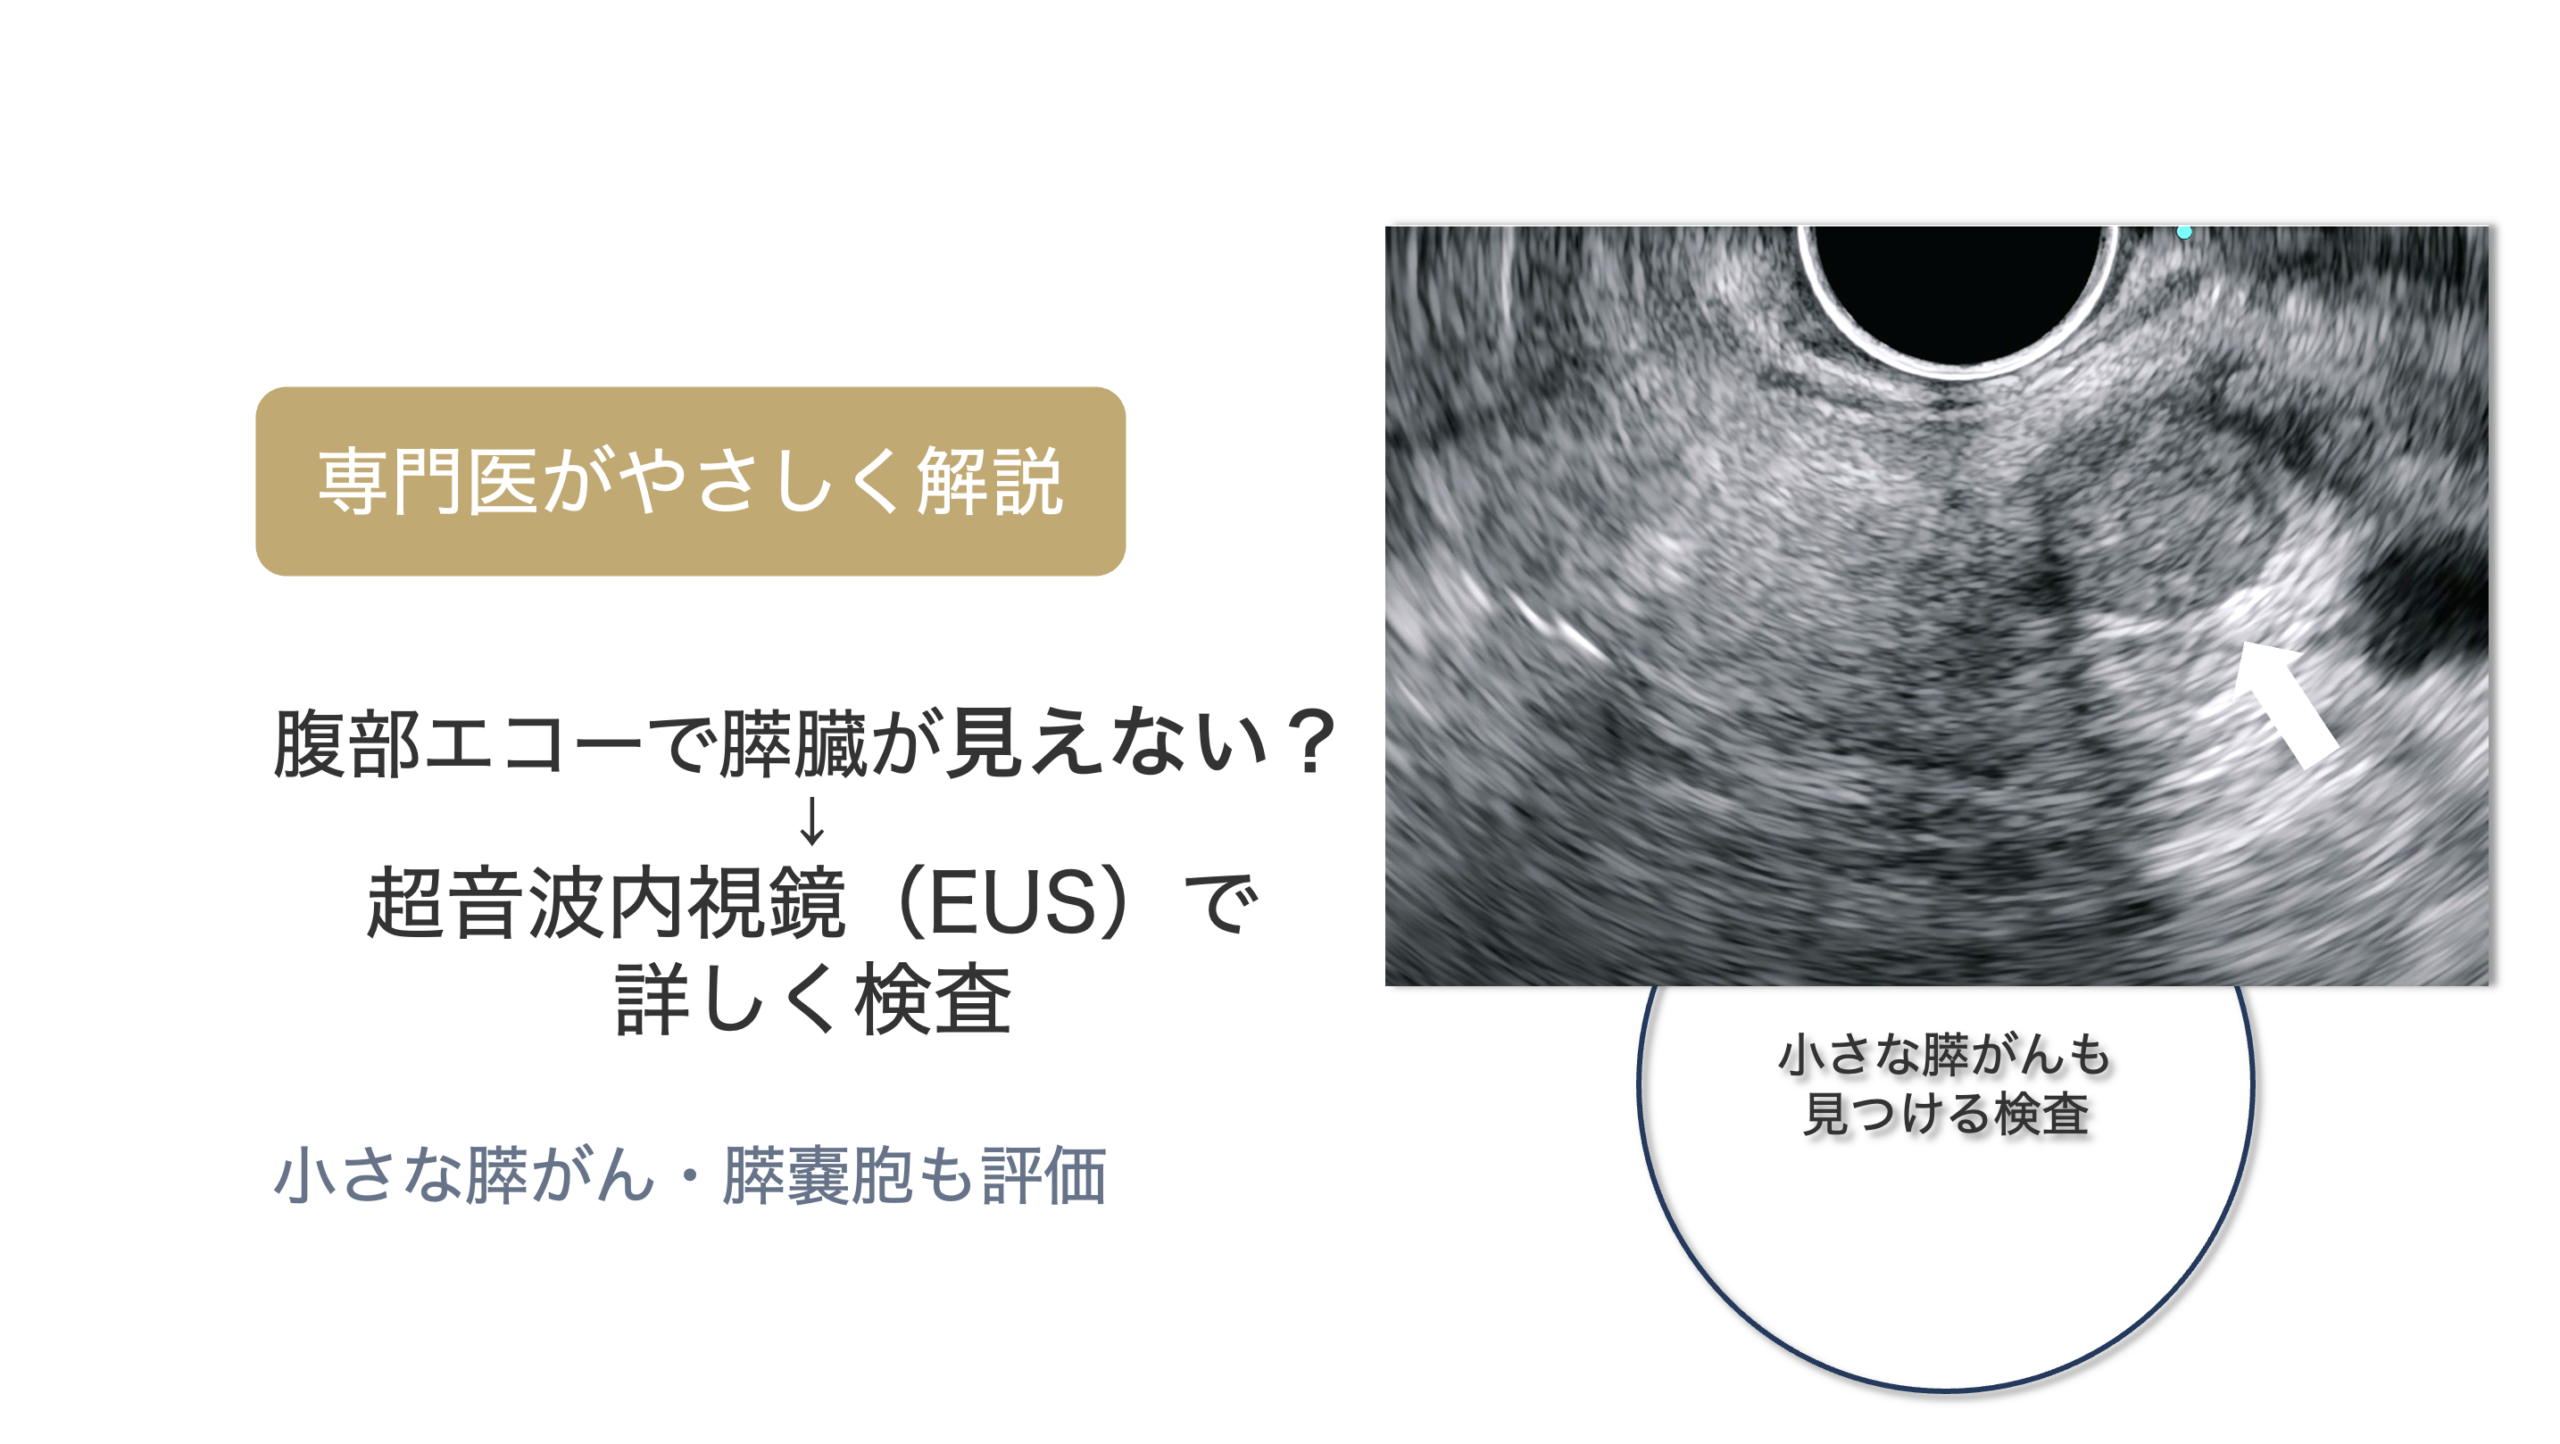

・超音波内視鏡検査(EUS)

胃カメラの先端に超音波を搭載した機器を用い、胃の壁の厚さや層構造を詳しく調べることができます。